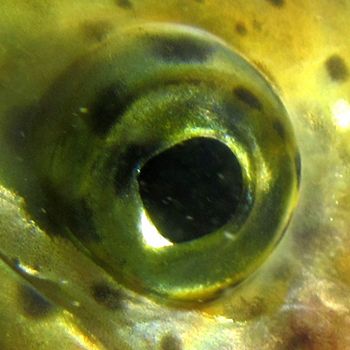

Healthy rainbow trout eye15

|